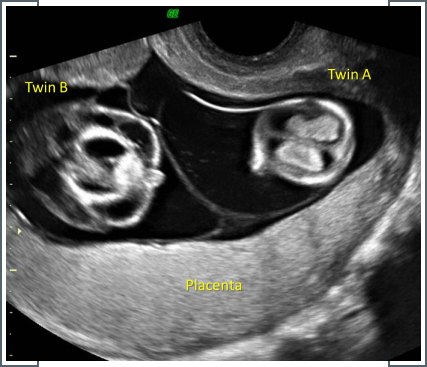

Müllerian anomalies ultrasound for multiple pregnancies and monochorionic twin pregnancy complications

Ultrasound for multiple pregnancies, particularly in cases of monochorionic twins or pregnancies complicated by Müllerian anomalies, is essential for assessing fetal development and monitoring potential complications. Müllerian anomalies involve structural abnormalities in the uterus, impacting fertility and pregnancy outcomes. In monochorionic twins who share a placenta, ultrasound helps detect complications like twin-to-twin transfusion syndrome, where blood flow between twins is imbalanced. Early detection through ultrasound enables timely intervention, ensuring proper management to mitigate risks such as preterm birth or developmental issues.